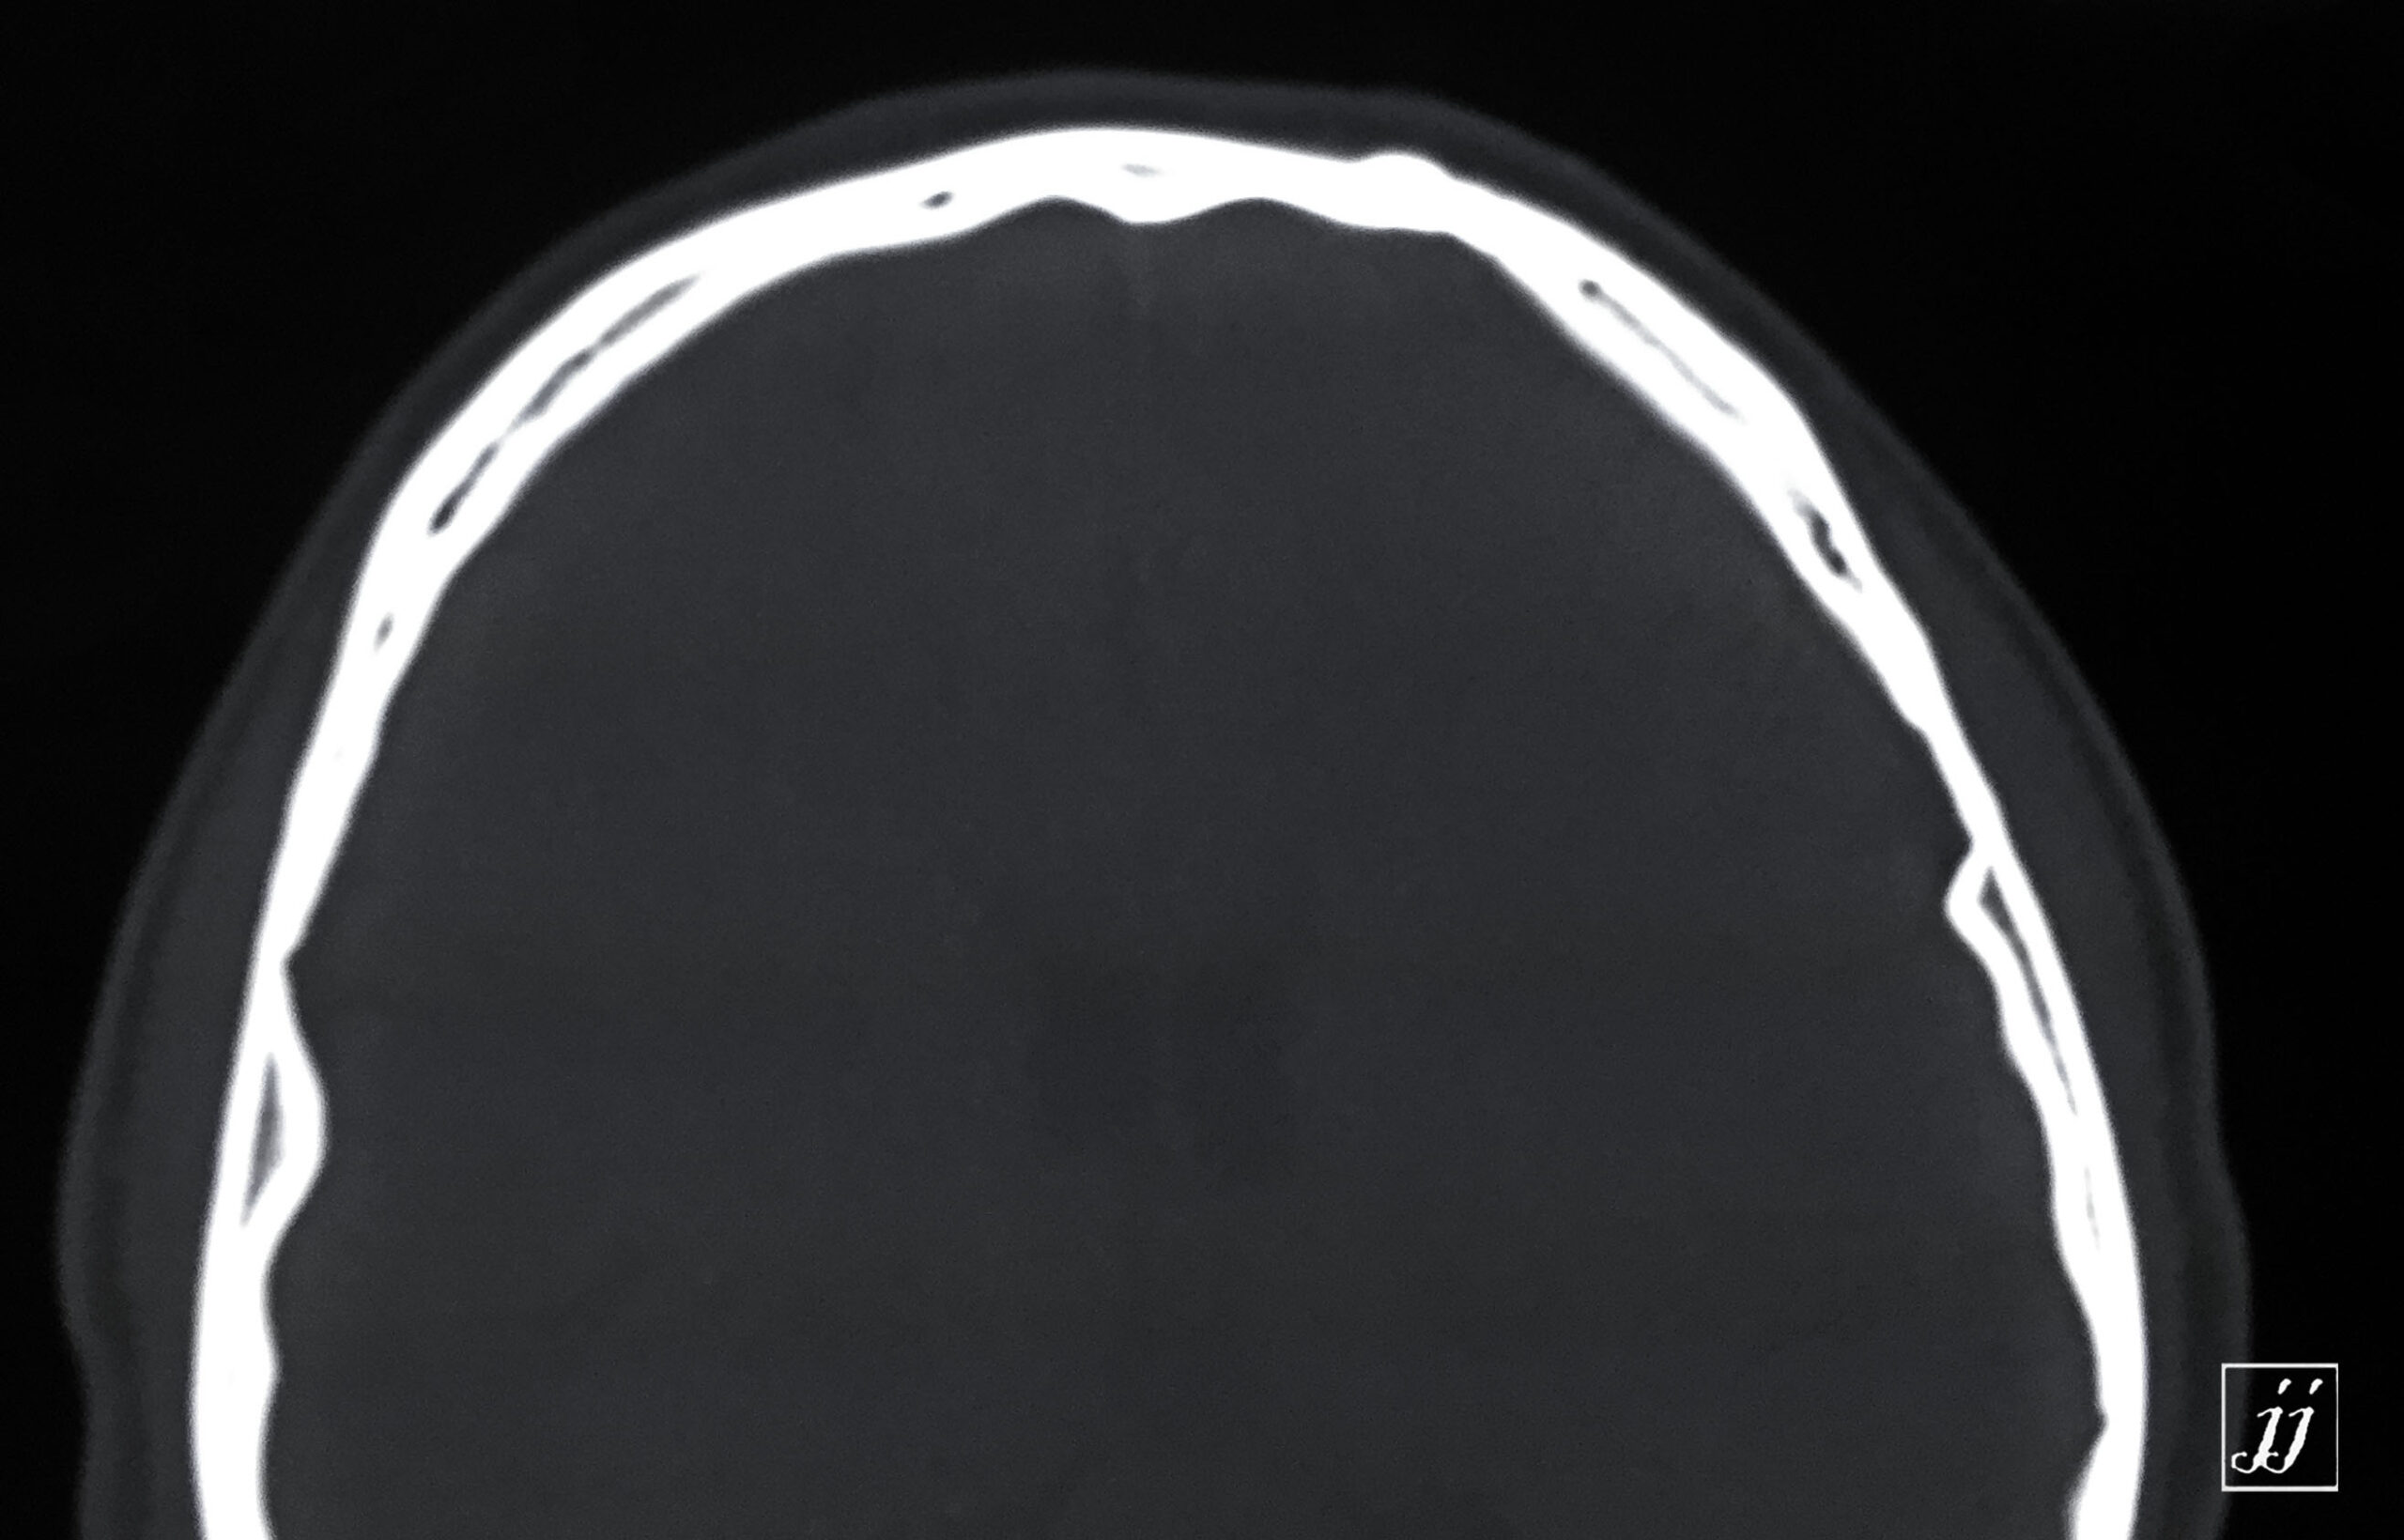

Brain- small osteoma (2)